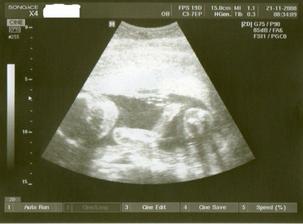

21.11. KO+velký ultrazvuk...........20+1 na velkém UTZ mimi v pořádku,jen se nám nechtělo ukázat.A dr.mě pro jistotu posílá ne genetický UTZ,objednala jsem se do Libereckého Genettu.Tam jedeme 28.11.

Tak jsme po UTZ,miminko se mlelo a krásně hýbalo,vše bylo vidět,vše je v pořádku a hlavně

JE TO KLUK....TAKŽE BUDEME MÍT MATYÁŠKA🙂))))))